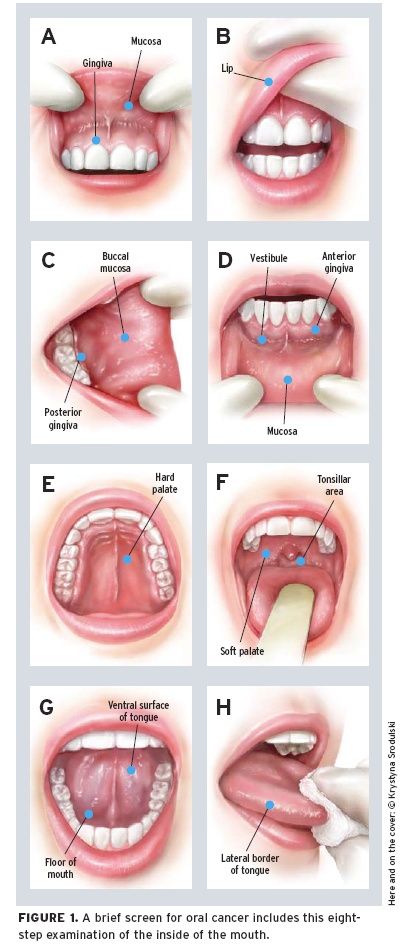

10 Steps To Perform An Oral Cancer Screening Dentistryiq

Making Oral Cancer Screening A Routine Part Of Your Patient

Self Oral Cancer Screening Socs Education Program School

Self Oral Cancer Screening Socs Education Program School

Self Oral Cancer Screening Socs Education Program School

Self Oral Cancer Screening Socs Education Program School

Self Oral Cancer Screening Socs Education Program School

Self Oral Cancer Screening Socs Education Program School

Six Step Screening Eva Grayzel

Faces Of Oral Cancer Six Step Screening